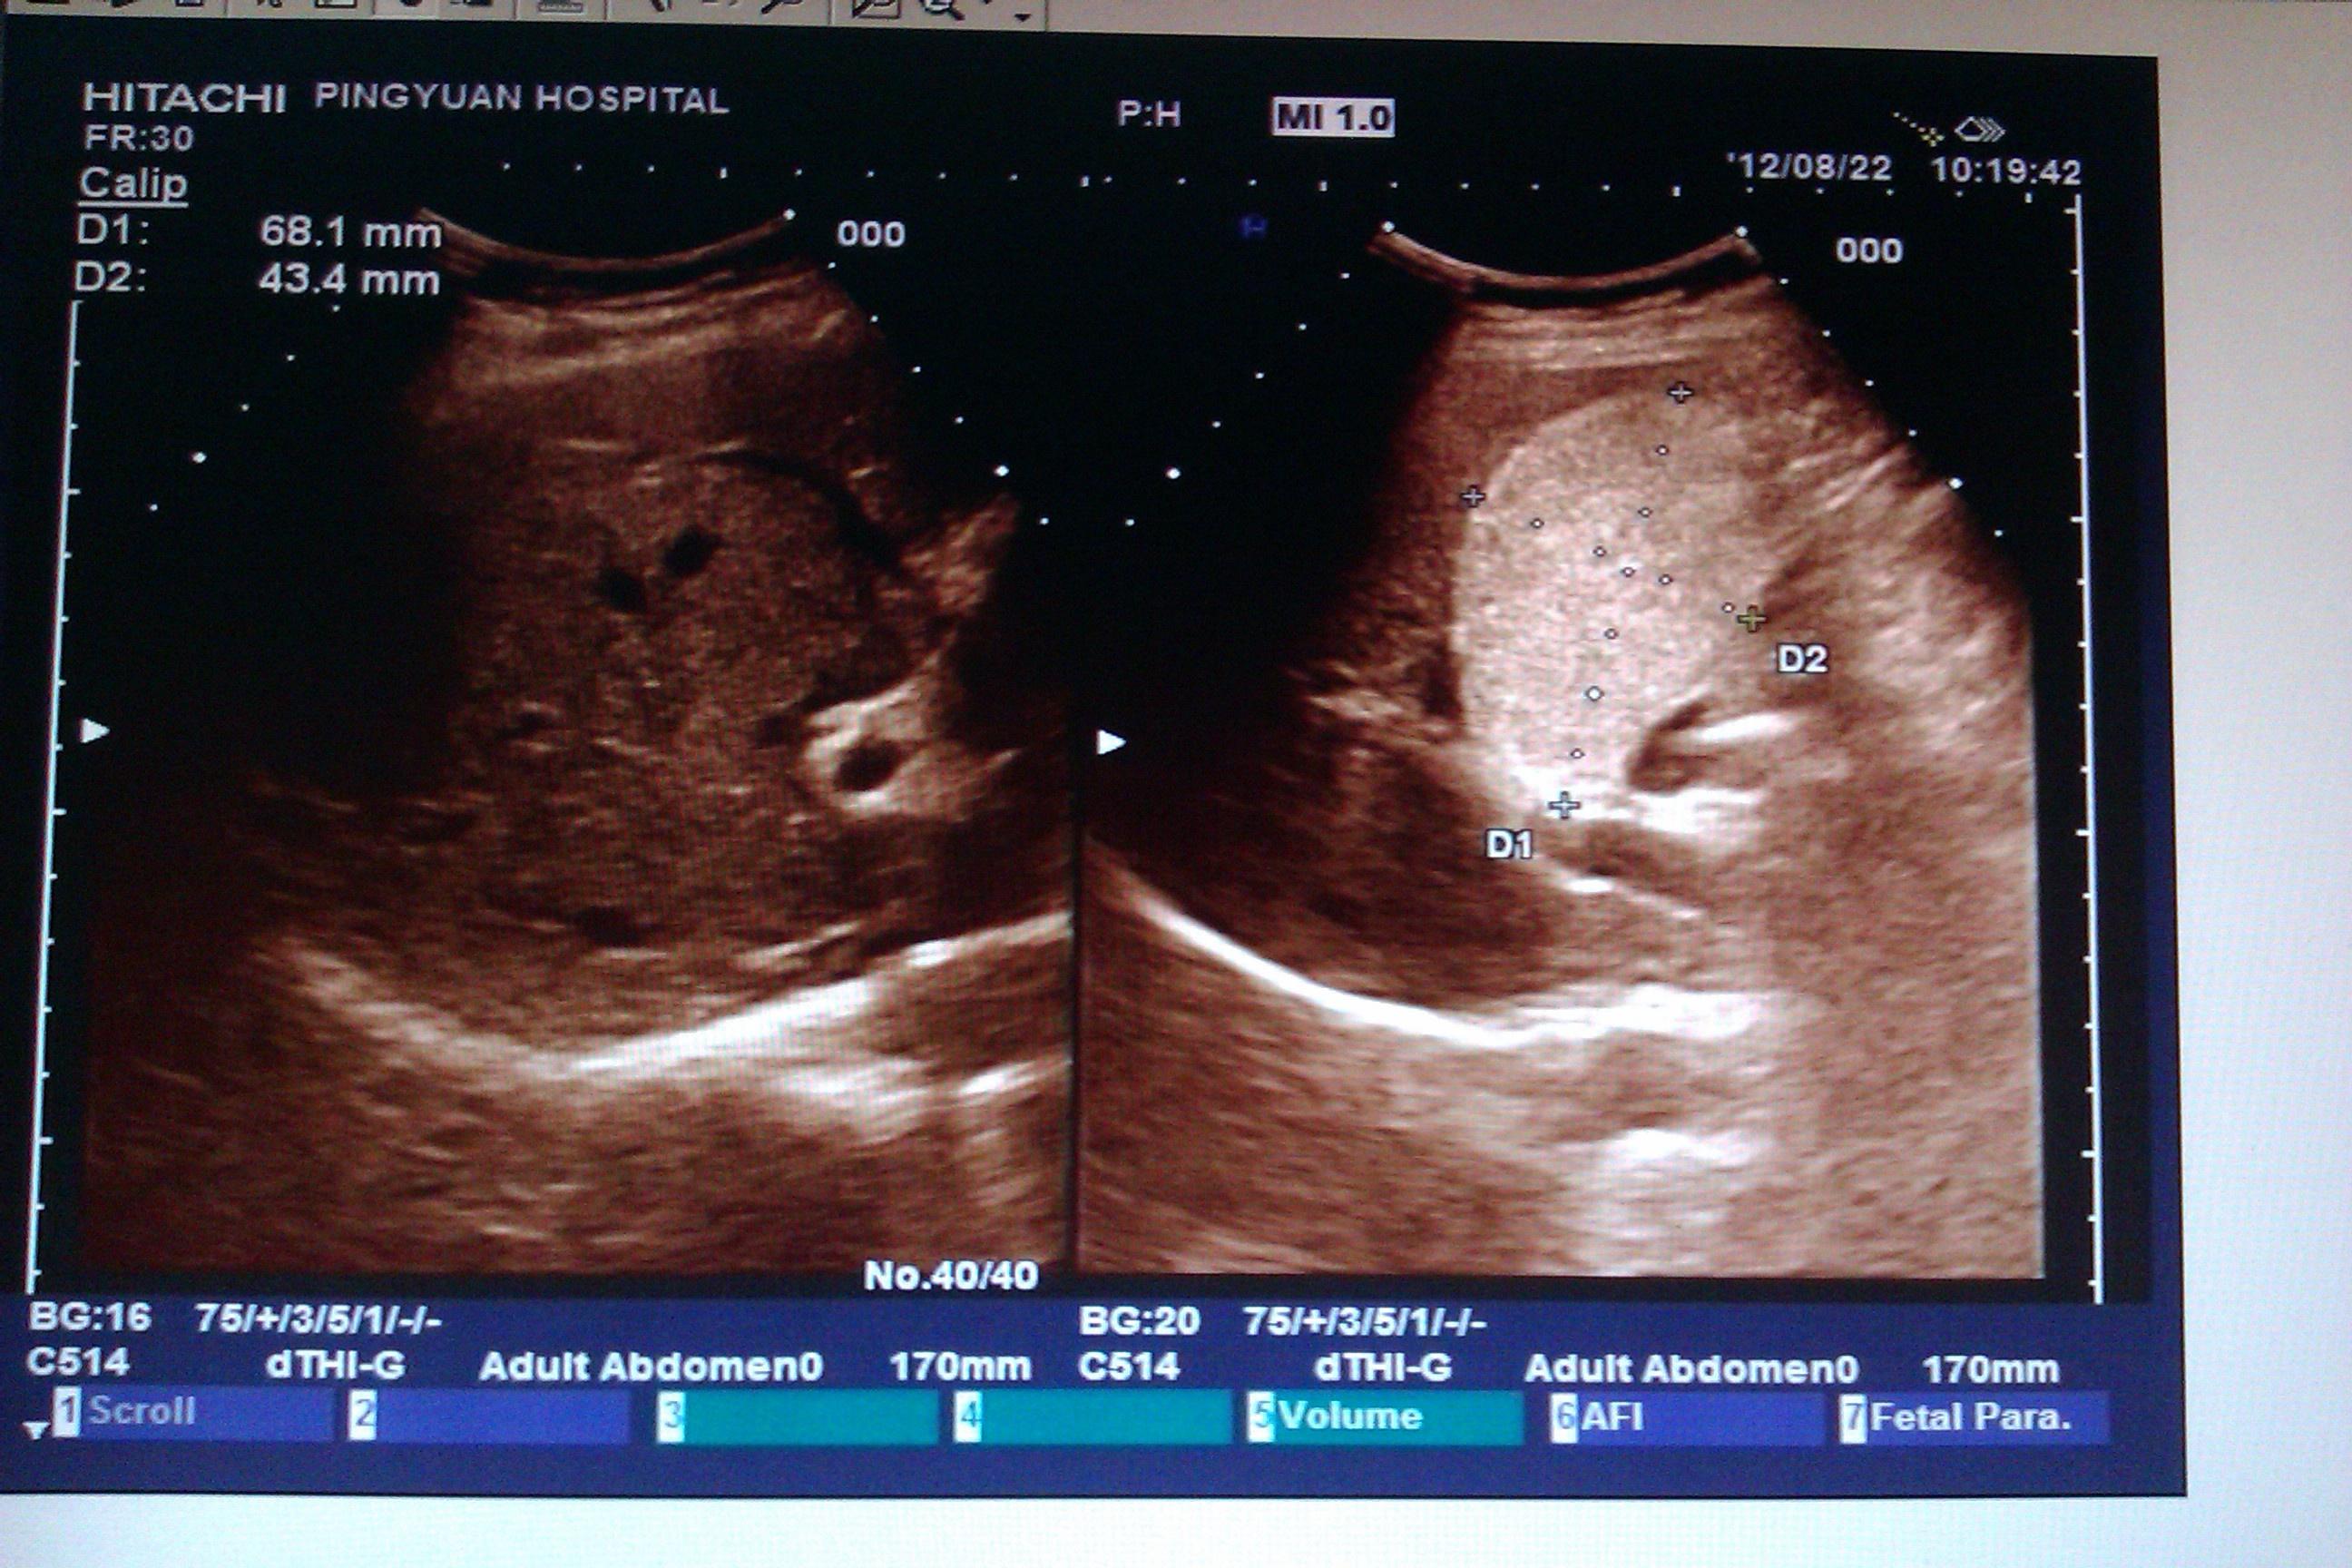

瓷器样胆囊 亳州市人民医院 影像中心